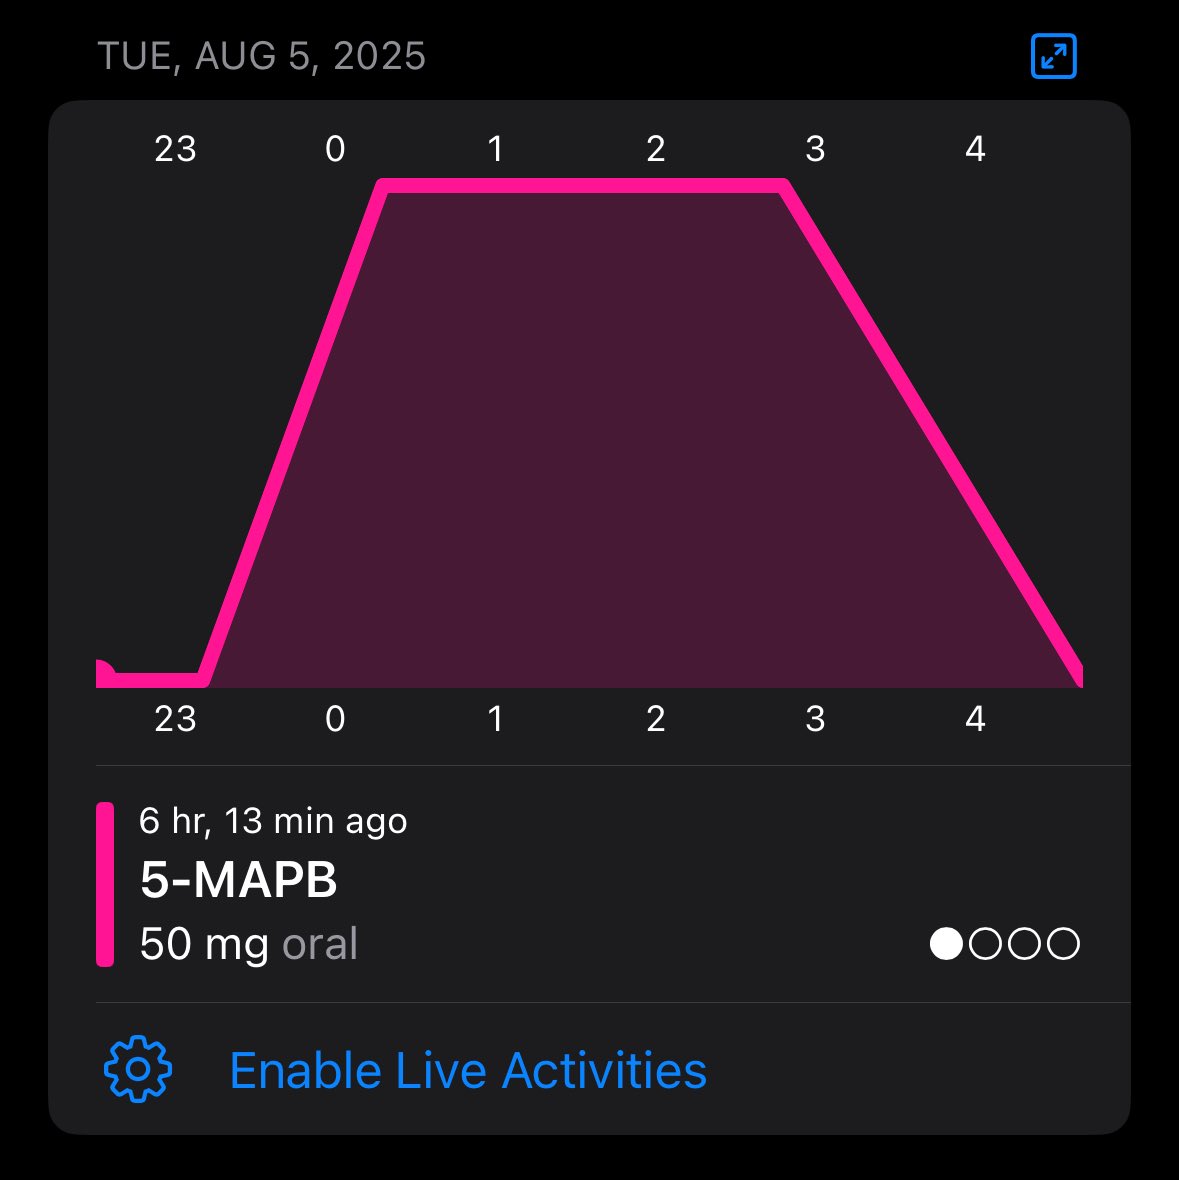

2025-08-05 20:49:11 UTC

每次用这一类都会持续比上面更长的时间,余辉的影响有时甚至在第三天

特别适合思考,不会像致幻剂那样影响语言和思维的流畅度,虽然也会比起平常没那么线性,好在对这种模式比较熟悉吧()以前用咖啡因都可以让思维弥漫开来 https://t.co/syx3QYDCJI

炽烈已极 @AnIncandescence@MMimeng72886 比如5-mapb,6-apb

2026-01-03 14:33:27 UTC

炽烈已极 @AnIncandescence@MMimeng72886 比如5-mapb,6-apb,mdma